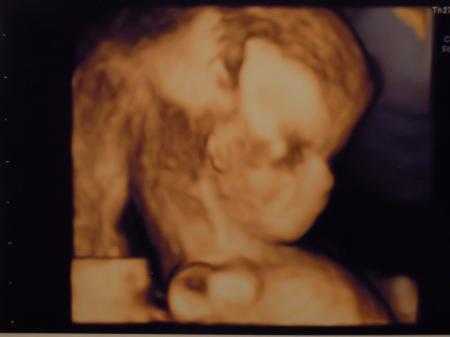

Und hier noch das 3D Bild. Lg ana